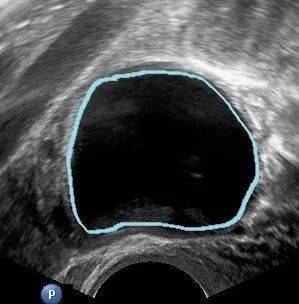

1、卵泡囊肿

当女性内分泌功能紊乱时,卵泡会发育不成熟,或成熟后不排卵,所以青春期少女和围绝经期女性容易出现卵 泡囊肿。并且,由于卵泡持续分泌雌激素,还可能引发子宫内膜增生过长、阴道不规则流血等。

这种情况一般可以观察2~3个月,在月经的第5~7天复查一下超声,有些卵泡囊肿可以超过5cm,持续存在数月 ,如果囊肿自行消退就无需治疗。